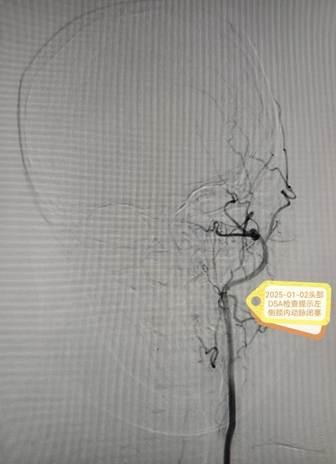

在麻醉科、手术室等多科室通力配合下,丁昊主任团队凭借丰富的经验与精湛的技术,顺利完成两阶段高难度手术。术后,李阿姨恢复良好,未出现神经功能损伤,脑血流显著改善,动脉瘤成功隔绝。护理团队全程实施个性化康复计划,从病情观察到心理疏导,从功能锻炼到生活护理,以专业与温情助力患者快速康复。

术后DSA结果